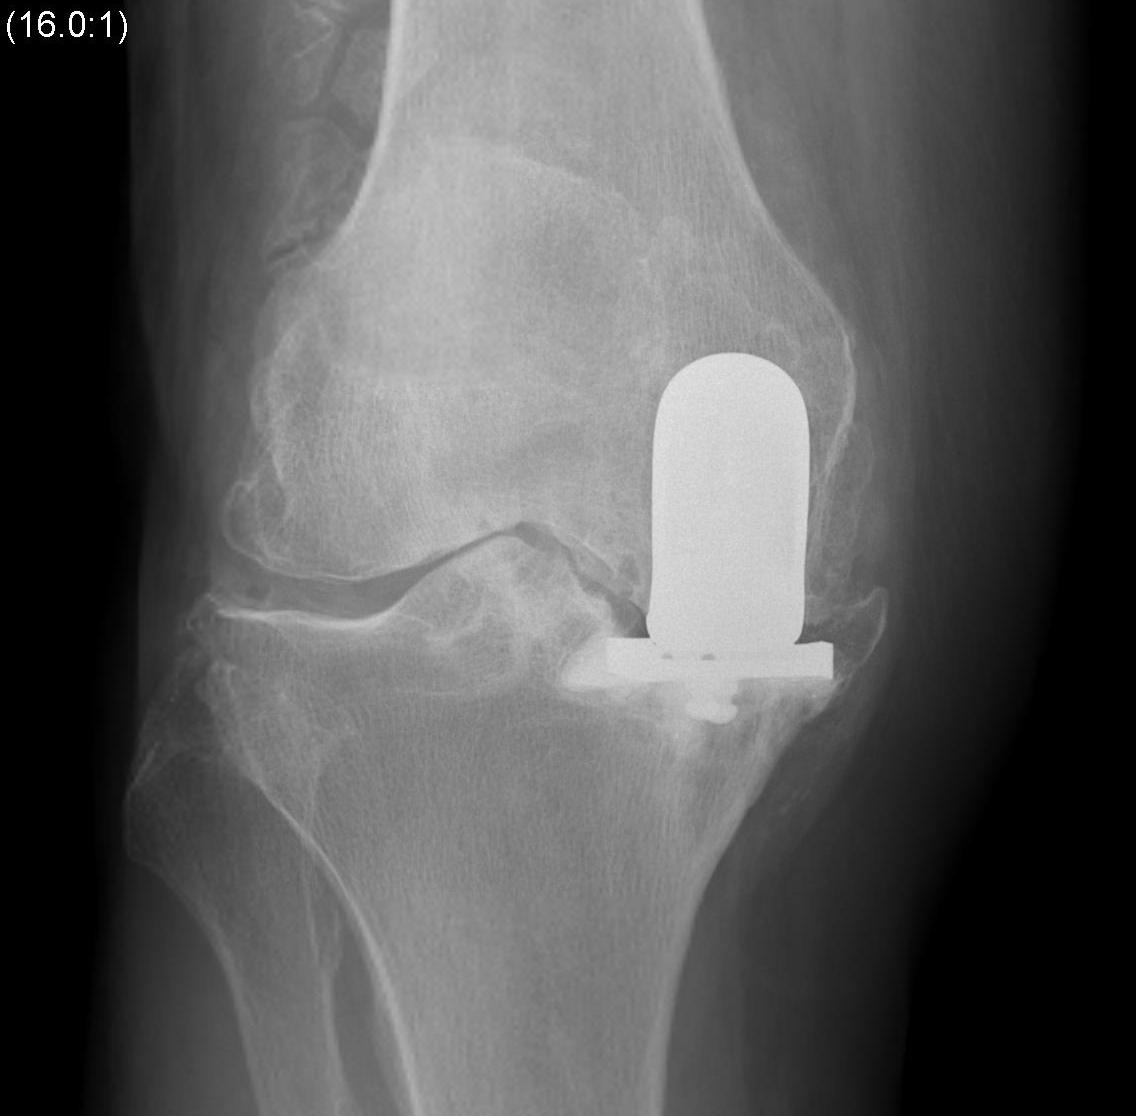

Patient 2